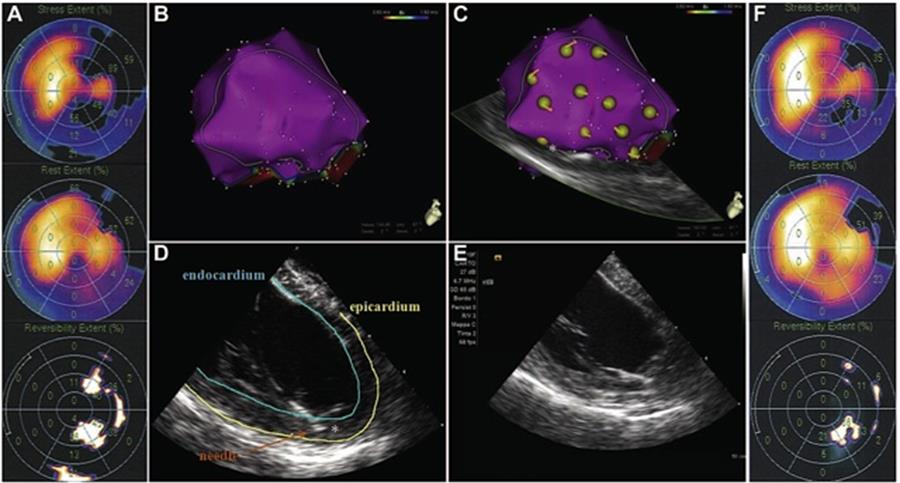

A) SPECT pre-intervento che mostra la presenza di un difetto ischemico reversibile. B) Mappa endocardica elettro-anatomica in 3D del ventricolo sinistro: nelle aree target, la mappa è caratterizzata da segnali normali (in viola) che escludono la presenza di cicatrici post-ischemiche. C) Le zone in giallo indicano i siti d’inoculazione al termine del trattamento. L'asterisco sulla mappa identifica la punta dell'ago. D) Ecografia intracardiaca (ICE) real-time che visualizza il catetere, evidenziando la posizione della punta dell'ago (asterisco) impegnato nella parete miocardica. E) ICE durante l’inoculazione delle cellule per escludere il rilascio significativo di microbolle all’interno della cavità. F) SPECT a 6 mesi dall’intervento, che mostra la significativa riduzione dell’ischemia nelle aree target.1

- Carbucicchio C, Casella M, Catto V, Bassetti B, Bestetti A, Pompilio G. Novel Application of 3-Dimensional Real-Time Cardiac Imaging to Guide Stem Cell-Based Therapy. Can J Cardiol 2015;31(8):1073.e13-5.